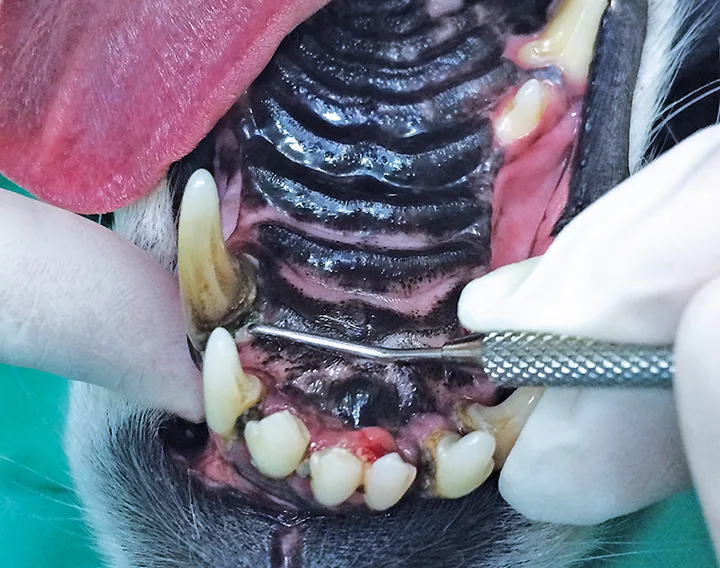

Canine mouth undergoing an anesthetic dental procedure.

FIGURE 1

With the patient under general anesthesia and in dorsal recumbency, dental charting and periodontal probing were performed on a tooth-by-tooth basis and revealed advanced periodontitis (PD4) at the right maxillary first and second incisor teeth and both maxillary canine teeth, with an oronasal fistula at the left maxillary canine tooth. The periodontal probe can be seen “disappearing” into the deep periodontal pocket/into the nose, which is characteristic of an oronasal fistula.

The oral cavity was rinsed with 0.12% chlorhexidine solution, and a complete oral examination using a UNC-15 periodontal probe and dental explorer was performed and supported by full-mouth dental radiographs. Detailed oral examination with the patient under general anesthesia confirmed bilaterally absent maxillary first and second premolar teeth (previously noted) with apparently intact soft tissue in the areas of missing teeth. Generalized moderate plaque and calculus accumulation were also confirmed and were associated with generalized moderate gingivitis. Mobility of 2 (ie, mobility over a distance of more than 0.5 mm and up to 1 mm)2 at the right maxillary first incisor tooth and mobility of 3 (ie, mobility over a distance exceeding 1 mm)2 at the right maxillary second incisor tooth with gingival recession of 4 mm and probing depth of 6 mm were diagnosed, confirming suspicion of advanced periodontitis. Physiologic mobility of a tooth is considered to be up to 0.2 mm, and normal/sulcal probing depth in a dog this size would be expected to be 1 to 2 mm.2 In addition, probing depth was >15 mm at the mesiopalatal aspect of the left maxillary canine tooth (Figure 1), which also had mobility of 1 (ie, mobility over a distance >0.2 mm and ≤0.5 mm)2; this had not been previously noted on the conscious examination. Bleeding from the left nostril occurred, which was suggestive of an oronasal fistula, likely the cause of the chronic unilateral nasal discharge. Probing depth at the mesiopalatal aspect of the right maxillary canine tooth was noted to be 10 mm, indicating advanced periodontitis at this tooth as well. The rest of the dental charting was within normal limits. Dental radiographs confirmed the clinical findings and revealed a retained root tip in the area of missing teeth (Figure 2).